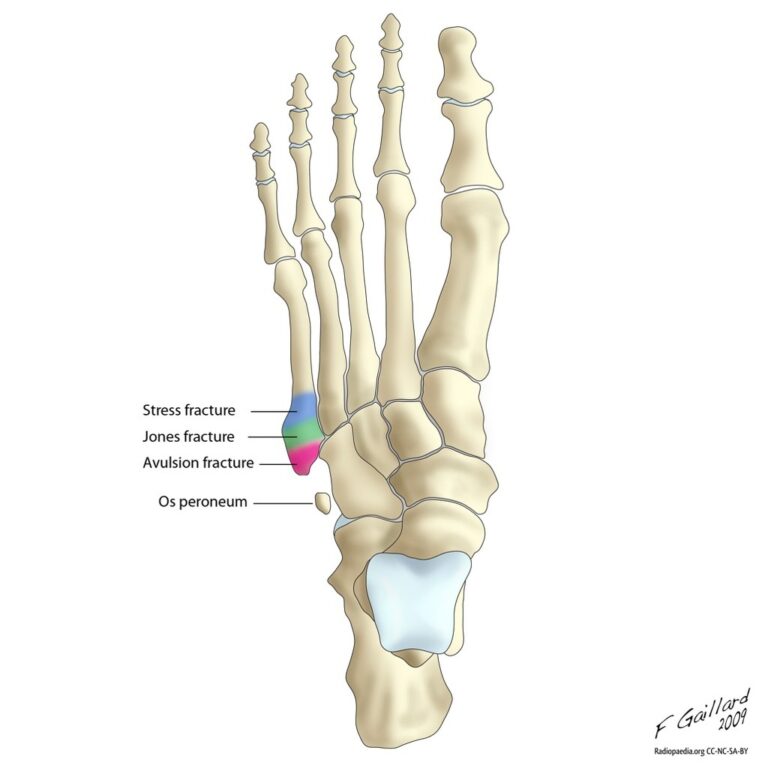

Las lesiones del fibrocartílago triangular: descripción y clasificación

Complejo fibrocartílago triangular: descripción y clasificación de las lesiones El complejo fibrocartílago triangular (su nombre en inglés: triangular fibrocartilage complex), conocido por su sigla CFCT, es una compleja estructura tanto desde el punto de vista anatómico como funcional-biomecánico. Las lesiones de esta estructura constituyen una causa frecuente de dolor en la región cubital…